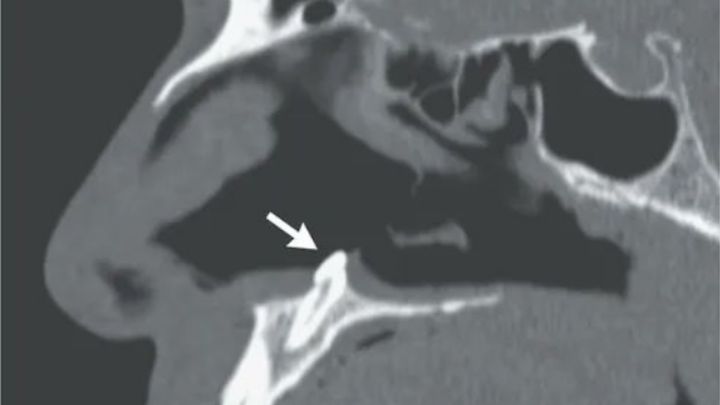

El caso ha sucedido en Nueva York. Tras una primera valoración no se encontró ningún problema de traumatismo o malformación facial, pero posteriormente, publica la revista médica, "la rinoscopia y la tomografía computarizada mostraron un 'diente ectópico' invertido en la cavidad nasal".

Posteriormente los médicos introdujeron una diminuta cámara en la cavidad nasal del paciente y se encontraron con una "masa blanca, dura, no dolorosa" que tras practicar una tomografía resultó ser un diente nacido dentro de la propia fosa nasal.

Antes esta situación se decidió practicar la extracción del diente, que medía 14 milímetros, "mediante un abordaje intranasal". Tres meses después de extirpar el extraño diente los doctores confirmaron que "los síntomas de obstrucción nasal del paciente habían desaparecido".